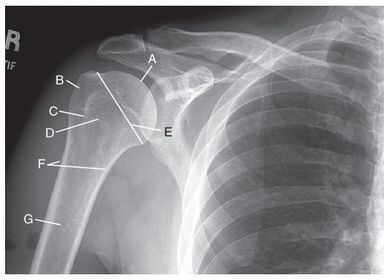

A. humeral head B. greater tubercle C. intertubercular groove (bicipital) D. lesser tubercle E. anatomic neck F. surgical neck G. humeral body